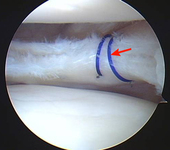

Arthroscopic view of horizontal cleavage tear of lateral meniscus (arrow)

From the collection of Dr Kevin R. Stone